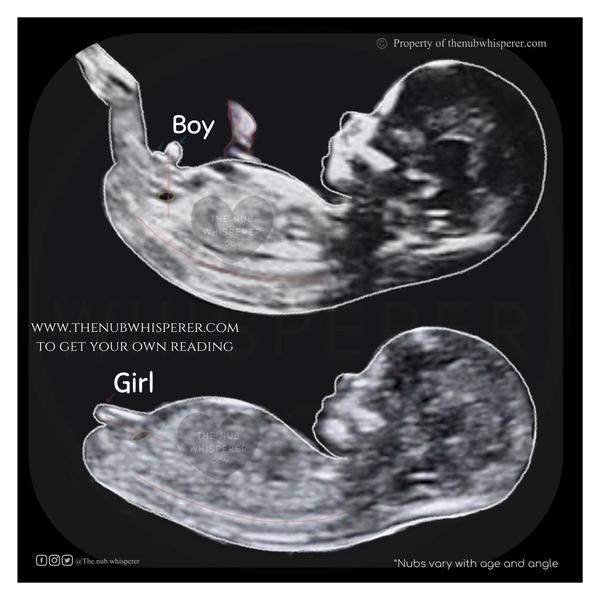

Baby🙏skúste poradiť prosím. Som 11+1 viem, ze je tu toho veľa, no vedeli by ste mi povedať prosím na aké pohlavie sa babenko rysuje? Aj skoro je viem, ale ten hrbolcek... Ďakujem

@bababibi nie som lekar ale toto mozno pomoze...podla mna dievca ale este je stradne malické, mozno tak za 2 tyzdne to uz bude viditelne. my cakame chlapca a v 13 tt to bolo uz jednoznacné